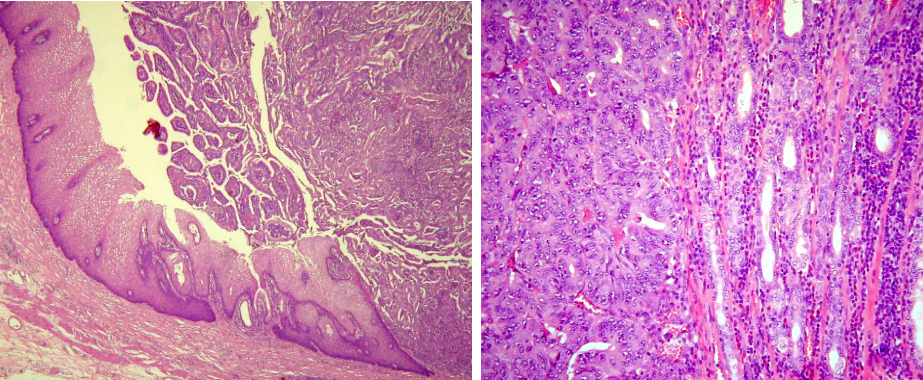

组织学可分为腺癌(乳头状或管状)伴不同程度分化、粘液腺癌、印戒细胞癌、未分化癌、腺鳞癌、鳞癌等。以腺癌为最多见,腺鳞癌、鳞癌见于直肠与肛管周围。

癌限于粘膜下层,无淋巴结转移称早期大肠癌。侵犯肌层者称进展期大肠癌,肉眼可分四型。

1.隆起型 或称息肉型、蕈伞型,肿瘤向腔内外生性生长,有蒂或无蒂,好发于右半结肠。

2.溃疡型 肿瘤表面形成溃疡,可深达肌层,外形如火山口状,伴坏死,好发于直肠和乙状结肠。

3.浸润型 肿瘤在肠壁各层浸润性生长,伴纤维组织增生,致肠壁增厚、狭窄,好发于直肠和乙状结肠。

4.胶样型 外观及切面均呈半透明胶冻状,好发于右侧结肠和直肠。